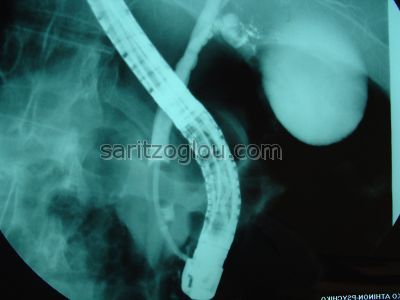

Σε συνέχεια της προηγούμενης εικόνας. Το μπαλόνι εξέρχεται από τον χοληδόχο πόρο αφαιρόντας τον λίθο από το τελικό άκρο του.